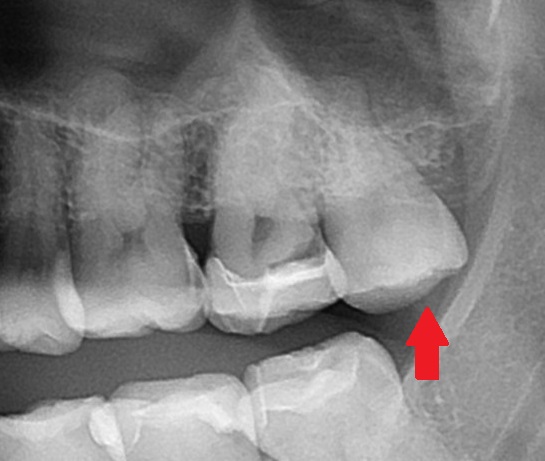

まずレントゲン写真(エックス線写真)を見てみましょう。

こちらのは歯は親知らずです(矢印)

一つ手前(左側)の歯はスケルトンのように見えますよね。

青い所がセラミックで、以前虫歯治療でセラミックを入れたようです。

赤く囲まれた所が黒く、虫歯があります。

さらに手前の歯の間も虫歯です(-_-;)

虫歯はレントゲン写真(エックス線写真)で確認ができます。

虫歯は歯が溶けてしまう病気なので、歯の内部が溶けて、

レントゲン写真で黒く写ってきます。